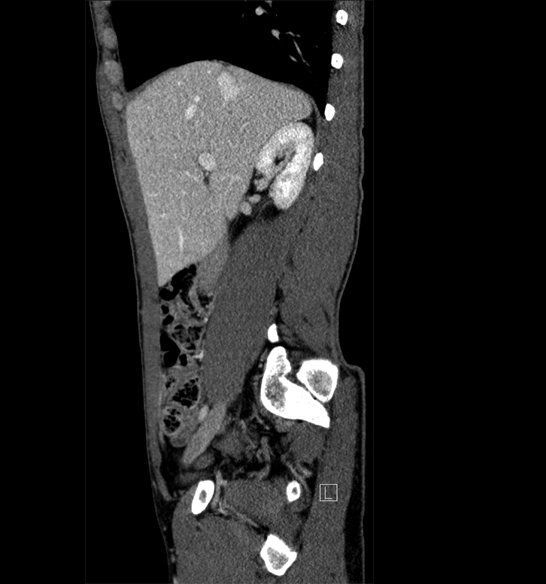

Body

Covers abdominal CT anatomy.